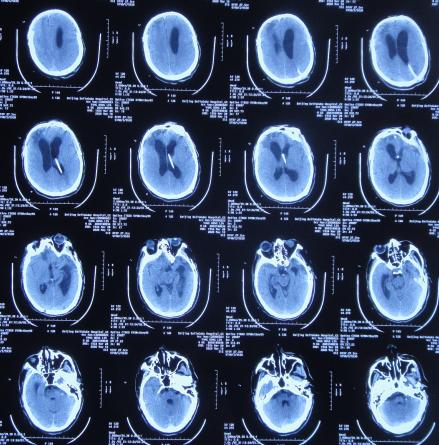

但拔除腰大池引流管后第2天就出现了发热,再次给予腰大池引流,但引流出淡红色浑浊脑脊液,且化验脑脊液示白细胞高,考虑颅内感染,脑脊液培养无细菌生长,给予抗菌素后3天后体温变正常。

第2次腰穿引流后11天即2020年1月14日,查头颅CT( 图-21 )后认为病情有好转,随后拔除腰大池引流管,计划明日第2次进行脑室腹腔分流术。

图-21: 2020年1月14日头颅CT

颅骨修补术后33天即第1次脑室分流管拔除后27天2020年1月15日,进行了第2次的脑室腹腔分流术( 图-22 )。

图-22: 2020年1月15日头颅CT

颅骨修补术后35天即第2次脑室腹腔分流术后2天2020年1月17日,病情稳定,查头颅CT( 图-23 )后认为无异常。

图-23: 2020年1月17日头颅CT

颅骨修补术后40天即第2次脑室腹腔分流术后7天即2020年1月22日(第2家医院住院治疗43天)出院,转住入第3家的北京某康复医院进行康复治疗。

在第3家医院康复治疗近1个月时间内,曾4次查头颅影像(2020年1月22日( 图-24 )、2020年1月29日( 图-25 )、2020年2月10日( 图-26 )、2020年2月19日( 图-27 ))均示脑室仍有扩张,但未给予特殊处理。

图-24: 2020年1月22日头颅核磁

图-25: 2020年1月29日头颅CT

图-26: 2020年2月10日头颅CT

图-27: 2020年2月19日头颅CT

但住院期间间断性发热仅给予药物后仍反复,且大小便时有*禁失**,因此于第3家医院治疗28天后即2020年2月19日,转回当地的第4家河北省邯郸市某三甲医院治疗。

在第4家医院治疗26天,仍间断性发热、大小便*禁失**加重,住院期间曾2次查头颅CT(2020年2月27日( 图-28 )、2020年3月12日( 图-29 ))示脑室仍扩张。

图-28: 2020年2月27日头颅CT

图-29: 2020年3月12日头颅CT

治疗期间给予抗生素,并多次腰椎穿刺,脑脊液培养示无菌,发热虽有好转但大小便*禁失**无改善,且意识变模糊。经当地医生介绍转住入北京北亚骨科医院的李小勇脑脊液科。